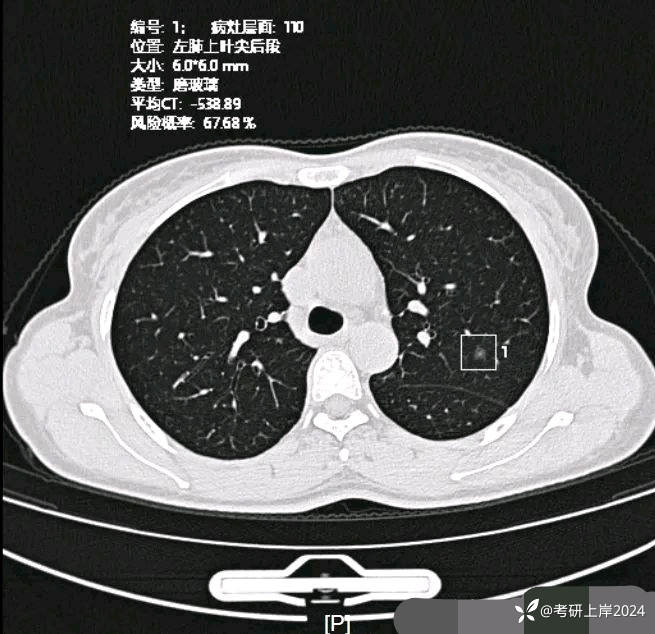

患者最近的检查有AI辅助诊断意见,找出的病灶分别如下:

病灶12:左上叶磨玻璃结节,轮廓较清,有血管穿行,考虑肺泡上皮不典型增生可能性较大,也可能原位癌;

病灶17:左上叶磨玻璃结节,伴小空泡征,也有微血管征,考虑原位癌可能性较大。

与2024年3月份复查时的对比,几乎没有变化。我的回复:两肺多达20几处结节,除了最后一处实性的考虑良性的,其他的都是磨玻璃密度,整体轮廓较清的,这在3月份的AI诊断上都有截图,其中最主要的几处就是我另外再截图了发来的这几处。它们也仍算是磨玻璃密度,病理大概会是原位癌可能性大,个把最坏可能是微浸润性腺癌,其实说不上明显实性成分,只是右上叶的那三处,最靠纵隔的那枚有血管穿过,显得像是混合密度,但肿瘤的成分仍是磨玻璃的。鉴于多发,又无法都通过手术全部切除,我的想法仍是再观察随访为主,待主病灶进展到有风险了再来考虑干预处理主病灶,并到时候兼顾同侧的其他结节是否顺带解决一部分。目前先随访,意见供参考!感悟:今天为什么要分享其实挺常见的这种多发磨玻璃病例?我想主要是由于结友问诊了这么多医生,仍在继续问,说明她虽然这些结节目前风险不大,但对她的心理造成了很大的压力,这也是结友最常见的心理状态。我觉得心理的崩溃或不断钻牛角尖的思考或许在短期内导致的害处更甚于结节本身!她问了这么多医生,肯定大部分都认为能随访,目前也没有风险大到定得赶紧处理的病灶,但她仍在不停的问诊,总想得到更让其踏实的答案。但哪位医生能说这些不是恶性范围的呢?谁能告诉她这是正常的呢?那不可能呀!已对查出多发结节,致病因素不明、预防措施没有、切又切不光、用药也不用!你说除了正确认识它、理性面对它,你能如何?在问诊中,总是有结友问到底有没有增长1毫米?CT值有没有增加?血管有没有进入?空泡有没有?实性成分有没有以及占多少?这些作为患者自己定要去纠结有何益?能说明什么问题呢?总体上,如果像今天这位结友医院提供AI辅助诊断意见,那是大小、体积、CT值、风险程度都会列的清清楚楚。但实际上在临床工作中,医生并不必这样按数值去判断风险或决定是否手术,如果这样还需要医生干嘛,AI全部会给出意见,AI说该开刀的转给胸外科、AI说可随访的回家下次来复查、AI说有风险的去消融等等。事实上我一直认为,我们看肺多发结节,关键就抓住:1、最主要的病灶风险如何:如果主病灶仍是危险性不高能随访,那么既无必要去数一共是10处还是15处,抑或20处,都没有意义,因为反正是按时复查就行;2、不同时期影像的对比,过于细微的差别,当其不足以改变临床决策的时候,就失去了深究的意义:纯磨只需随访的,你是5毫米也好,7毫米也罢,有何相干?反正仍不需干预处理。实性结节怕它危险,但若2毫米、3毫米,连影像特征都看不明白,更不可能为了这类结节去切下来化验,那么总在担心到底良性还是恶性,会不会是小细胞癌有何用?所以我在临床工作中,基本上不在意具体大小,也不去测CT值,关注一是实性成分有没有;二是血管有没有进入以及异常增粗;三是对比最早的与最近的有没有明显变化。放平心态、理性面对,该随访时按时随访,该干预时下决心干预!